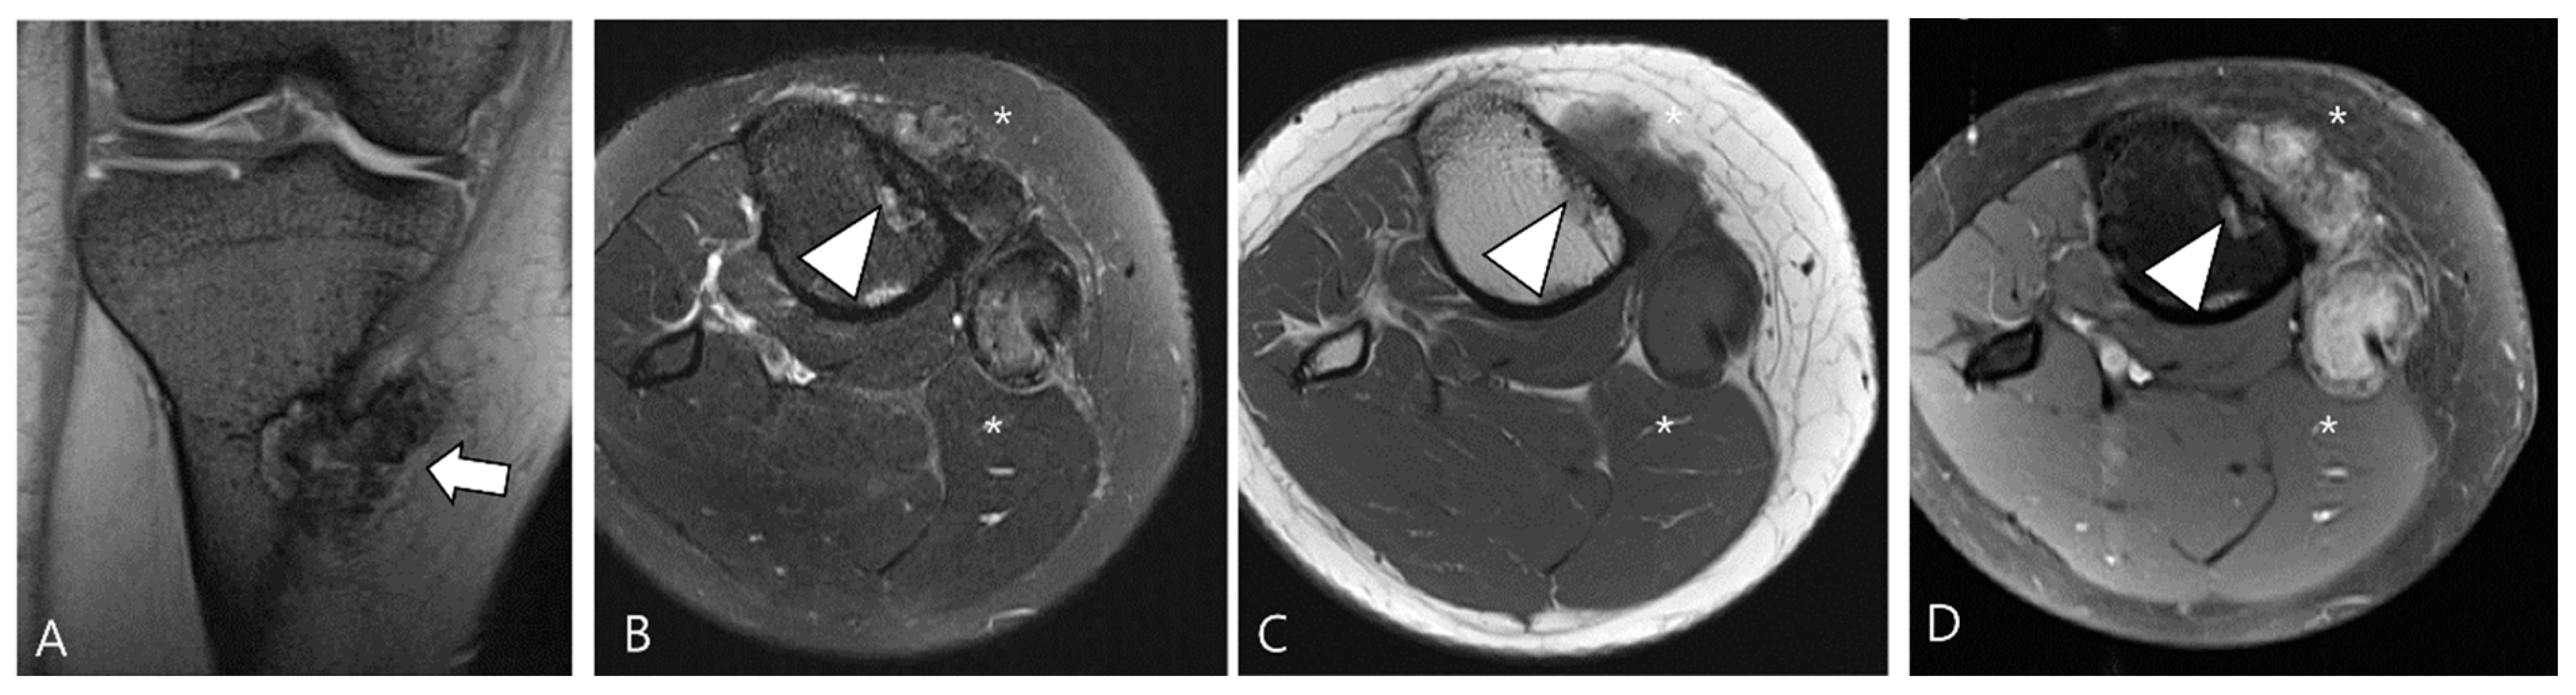

4. MRI Findings for D-TSGCT on Follow-Up MRI

4.2. Checklists on Follow-Up MRI for D-TSGCT